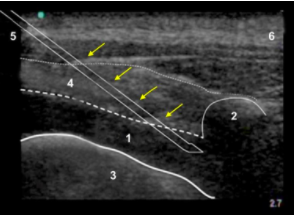

傍脊椎、麻酔の広がりの画像

局所麻酔の広がり

横断プロセス

胸膜

外肋間筋

外側

内側

黄色の矢印 – 針